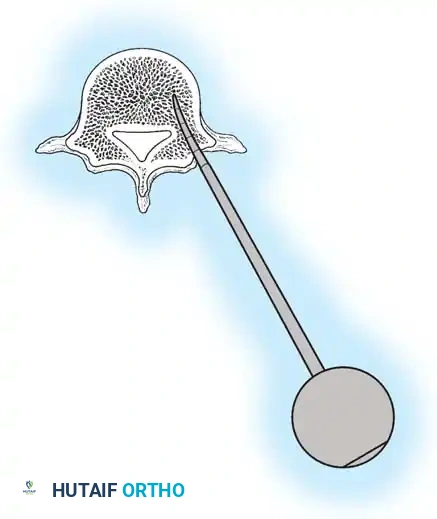

The Moe Technique (Thoracic Spine)

The Moe technique is a highly effective method for achieving intra-articular arthrodesis in the coronally oriented thoracic facet joints.

Fig. 38-26: The Moe technique of thoracic facet fusion, demonstrating the creation of hinged bone flaps.

- Expose the spine fully to the tips of the transverse processes.

- Using a sharp osteotome or Cobb gouge, begin a cut over the cephalad articular process at the base of the lamina.

- Carry this cut along the transverse process almost to its tip. Bend this cortical fragment laterally so it lies between the transverse processes, ideally leaving it hinged on its lateral periosteal attachment to preserve local vascularity.

- Thoroughly denude all articular cartilage from the superior articular process using a sharp curet.

- Make a secondary cut in the superior articular facet, working medially to laterally, producing another hinged fragment.

- Pack the resulting intra-articular defect tightly with cancellous bone graft.